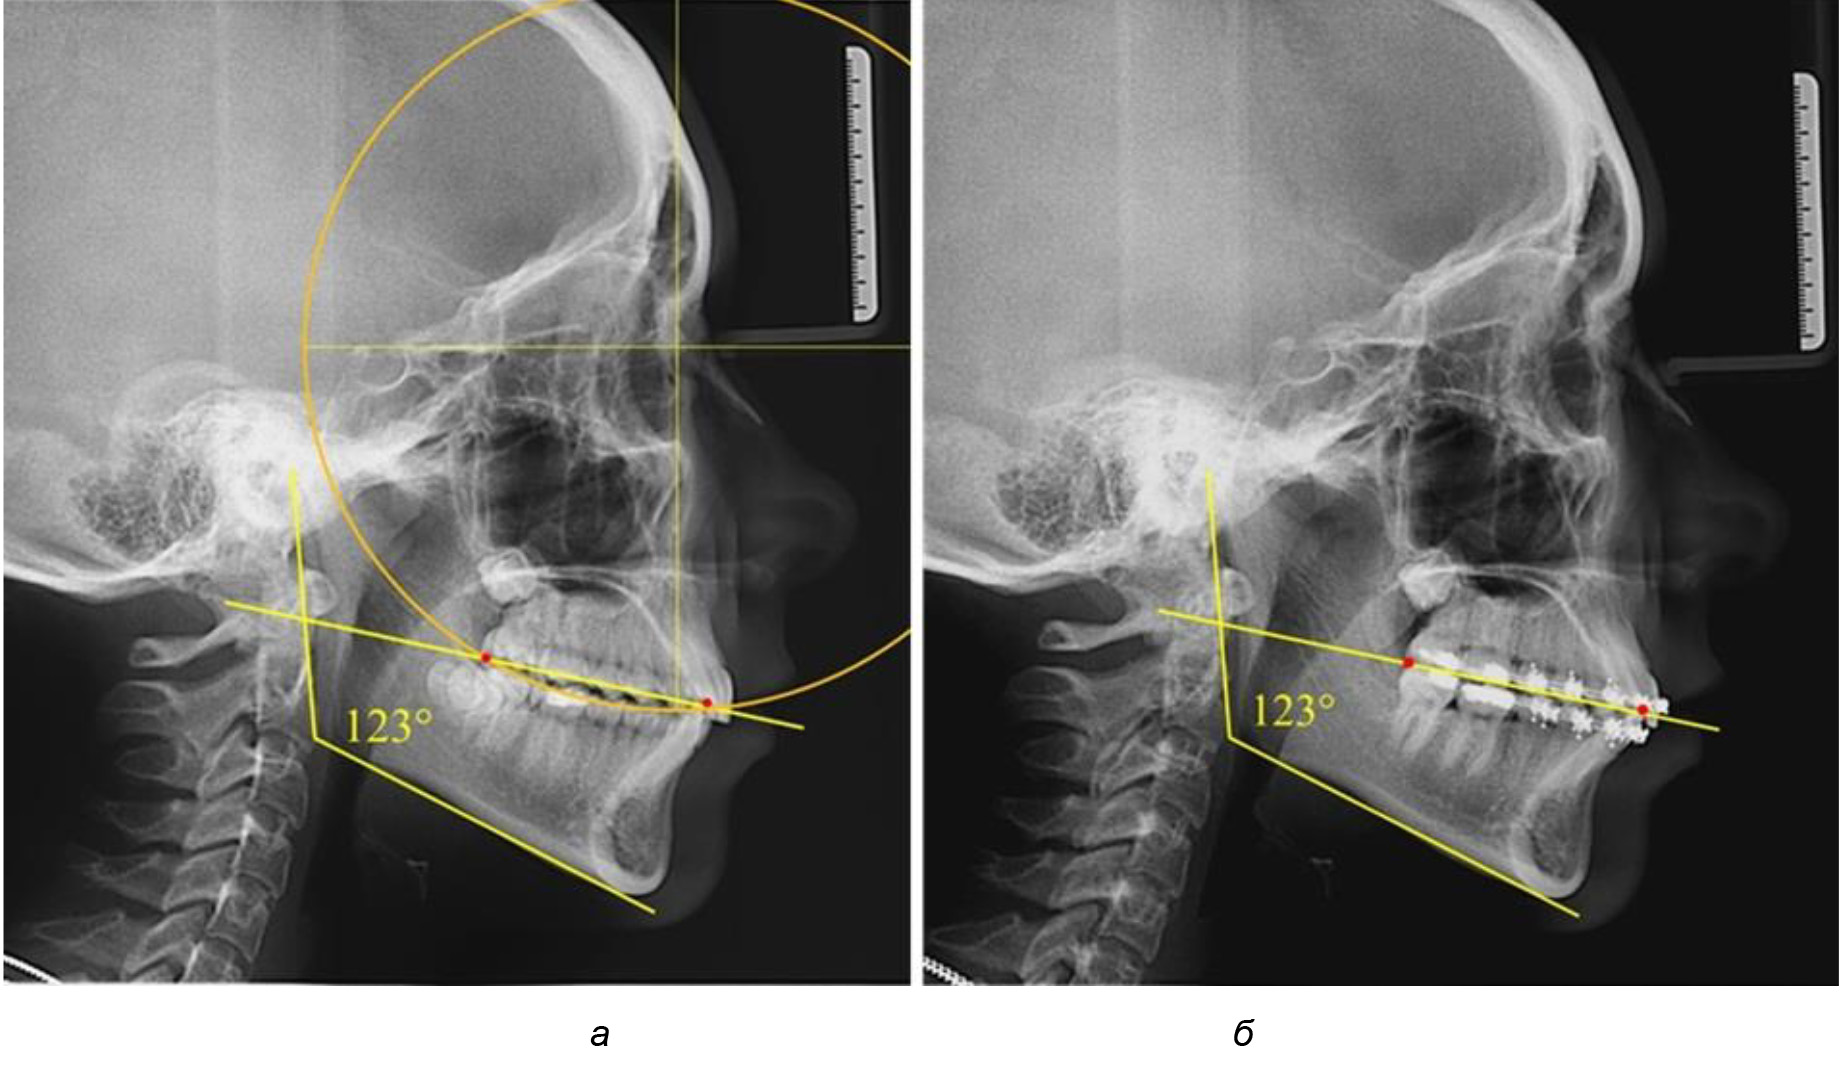

В 3-ю подгруппу вошли ТРГ и ОПТГ 14 человек 1-й группы, что составило (22,58 ± 5,31) % от общего количества людей 1-й группы. Величина угла нижней челюсти в среднем составила (114,85 ± 2,87)° и характеризовала горизонтальный тип нижней челюсти.

Глубина кривой Spee в среднем по 2-й подгруппе составил (2,94 ± 0,47) мм, что было меньше, чем в других подгруппах. Деление величины радиуса круга к длине окклюзионной линии составило 1,616 ± 0,02 (рис. 4).

Рис. 3. Особенности кривой Spee на ТРГ (а) и ОПТГ (б) при нейтральном типе роста нижней челюсти

Рис. 4. Особенности кривой Spee на ТРГ (а) и ОПТГ (б) у людей с горизонтальным типом лица